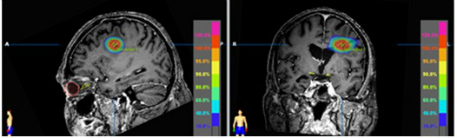

Stereotactic radiosurgery and stereotactic radiotherapy - SRS and SRT

SRS and SRT deliver very high dose radiotherapy with extremely precise margins. This allows you to get the maximum gain from your therapy by treating the tumour effectively, while keeping the effects to surrounding healthy tissue to a minimum.

We're one of 16 centres in the UK to offer this treatment. It's used for patients with small brain tumours, functional abnormalities of the brain and brain metastases.